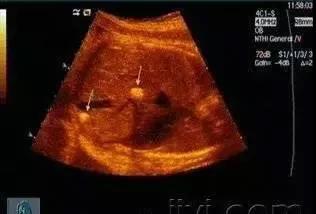

肝内钙化灶到底是怎么回事?

经常有病人持超声或者CT报告到门诊咨询,肝内钙化灶到底是怎么一回事。有些人认为得了肝内胆管结石,更有甚者认为是癌症,终日惶恐不安。

其实,肝内钙化灶是肝实质细胞炎症后形成的"",一般无大碍,一般不需治疗。

肝内有钙化点可能是肝内胆管壁部分钙化。它的原因多由于炎症、结核等引起,也可能是肝内钙化灶及肝组织局部坏死后的纤维化瘢痕。

肝内钙化灶它与肝内胆管结石一个最重要